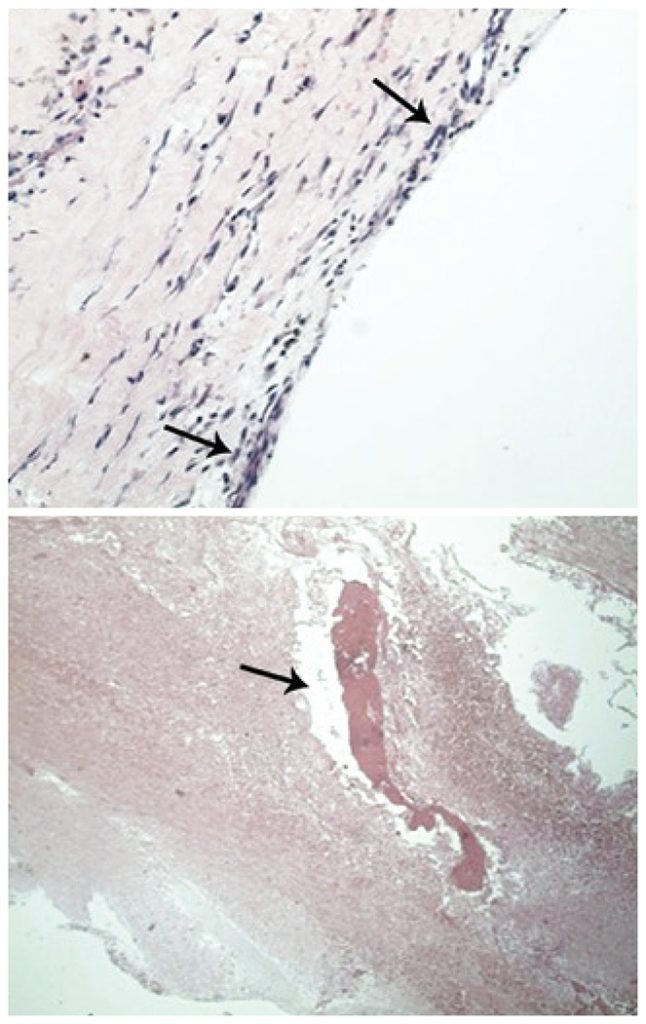

Cistos sinoviais da coluna lombar são uma causa incomum de dor na coluna e radiculopatia, geralmente com evolução gradual dos sintomas, que são secundários ao comprometimento do canal vertebral. Raramente, há hemorragia intracística, que pode se manifestar de forma aguda com síndrome compressiva radicular ou mesmo medular. Habitualmente, os cistos sinoviais associam-se a doença degenerativa facetária, embora a patogênese não esteja completamente estabelecida. Relatamos aqui um caso em que uma complicação hemorrágica em um cisto sinovial no nível L2-L3, adjacente à interfacetária direita, causou dor lombar e radiculopatia em um paciente em terapia anticoagulante, sendo necessária a ressecção cirúrgica.